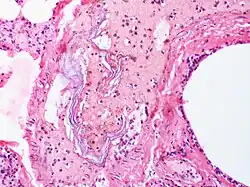

Rozpoznaje się go na podstawie badania sekcyjnego, podczas pośmiertnego badania histopatologicznego w płucach matki znajduje się płyn owodniowy lub elementy morfotyczne płodu[8]. Jest także możliwość diagnozy u kobiet, które przeżyły zator, na podstawie badania próbki odwirowanej krwi pochodzącej z naczyń płucnych matki (pobranej z żył ośrodkowych) lub po znalezieniu elementów naskórka płodu w plwocinie. Badania te przeprowadza się wyłącznie w sytuacji, gdy stan matki jest ciężki. Znajduje się również grono naukowców, którzy przyznają, że diagnozę można postawić, opierając się tylko na objawach klinicznych. S. Clark podaje opis triady objawów: niedociśnienie, niedotlenienie i zaburzenia koagulacji. Istnieją również podejrzenia zatoru płynem owodniowym u zdrowych kobiet, gdy w sytuacji porodu, cięcia cesarskiego lub bezpośrednio po nim rozwija się niewydolność oddechowa lub krążeniowa[9][10][11].